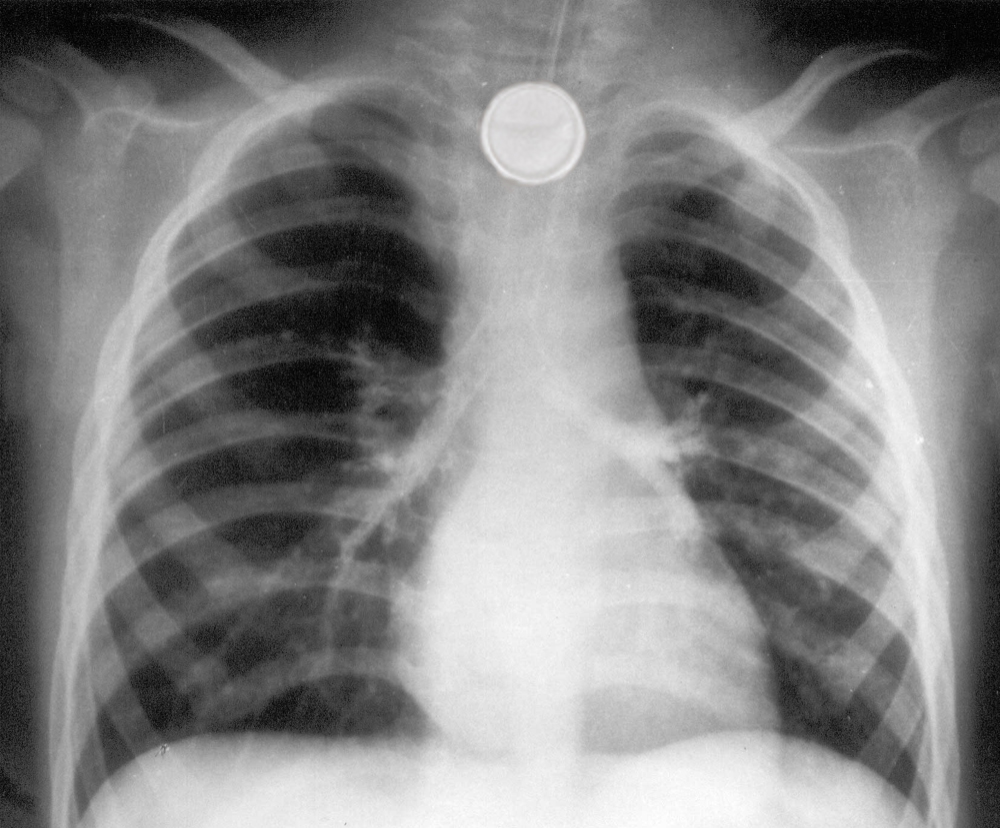

Child swallows a button battery? Feed honey on way to ER